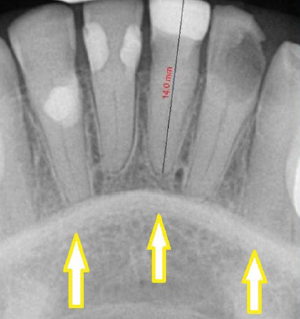

65. What is the anatomical structure indicated by arrow in this radiograph?

Incisive Foramen ( Nasalpalatine or anterior palatine foramen ) -The oral terminus of the nasalpalatine canal. - projected b/w roots and region of the middle and apical thirds of the central incisors. -potential site for cyst formation. - Presence of a cyst is predumed if the width of the foramen exceeds 1 cm.

69. What is the anatomical structure indicated by arrow in this radiograph?

Intermaxillary Suture (median suture) a thin radio lucent line in the midline on periapical radiographs between the two portions of the premaxilla. It extends from the alveolar crest between the central incisors superiorly through the anterior nasal spine and continues posteriorly between the maxillary palatine processes to the posterior aspect of the hard palate